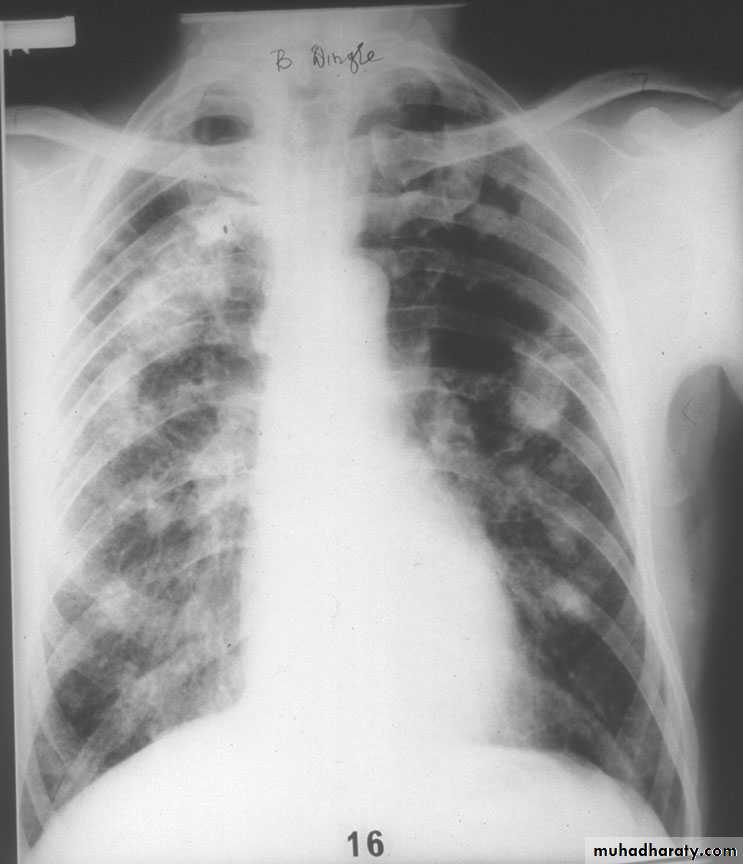

2-Complicated pneumoconiosis; large dense masses appear mainly in the upper lobes (also known as progressive massive fibrosis, PMF). Presented as cough, production of sputum, that may be black (melanoptysis) and breathlessness. Respiratory failure after cessation of exposure and right ventricular failure.

3-Caplan's syndrome describes the coexistence of rheumatoid arthritis and rounded fibrotic nodules 0.5-5 cm in diameter.